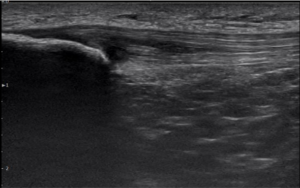

One of the most valuable tools I use in my practice is diagnostic musculoskeletal ultrasound.

Unlike static imaging, ultrasound allows us to:

- Visualize the tendon in real time

- Assess its structure and quality

- Correlate what we see with your symptoms and movement

This helps answer critical questions:

- Is the tendon acutely irritated or more chronically changed?

- Is there a mismatch between your symptoms and the tissue’s appearance?

- How does the tendon respond during movement?

This level of detail allows for a much more precise and personalized treatment plan.